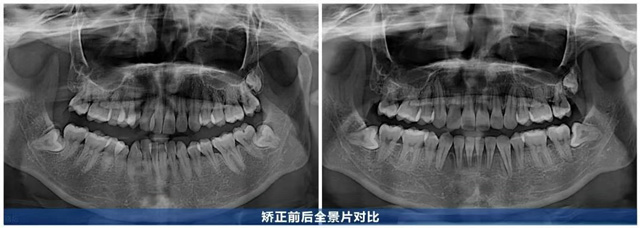

歷時(shí)2年,何女士的牙齒煥然一新:曾經(jīng)擁擠的牙齒排列有序,前牙深覆合改善,咬合關(guān)系恢復(fù)正常,笑起來牙弓弧度流暢自然,笑容更舒展了。從正面看,牙齒排列與唇形勾勒出協(xié)調(diào)的“微笑曲線”,上前牙顯露量恰到好處,牙齦幾乎不外露,面部線條更柔和,笑容也更顯柔和自信。